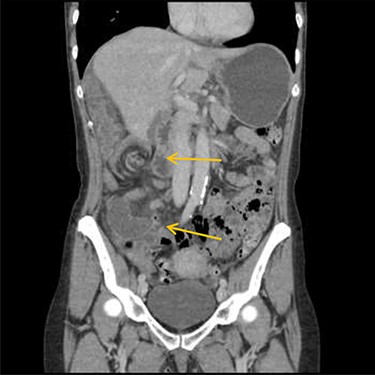

Emergency diagnostic laparoscopy was performed and findings were: 180 degree volvulus of terminal ileum, cecum and ascending colon overlapped each other and overriding the right loop of the liver, the lateral attachment of the right colon was long dilated and floppy (Figs 5 and 6). The dudeno-jejenal flexure was malrotated and lying in left upper quadrant just below to splenic flexure. Three congenital bands were found tilted around the terminal ileum, cecum and base of the appendix. Turbid free fluids with no evidence of infection also noted in the right upper quadrant and right para-colic gutter (Fig. 7). Otherwise, bowels were found healthy and viable. A healthy retrocecal and subserosal appendix was also noted intraoperatively. We converted to open Laparotomy and proceeded with right hemicolectomy due to complex intraoperative findings. The postoperative period was uneventful, and patient was discharged at home on postoperative Day 7.

Showing 180 degree volvulus of terminal ileum, cecum and ascending colon overlapped each other and overriding the right loop of the liver.